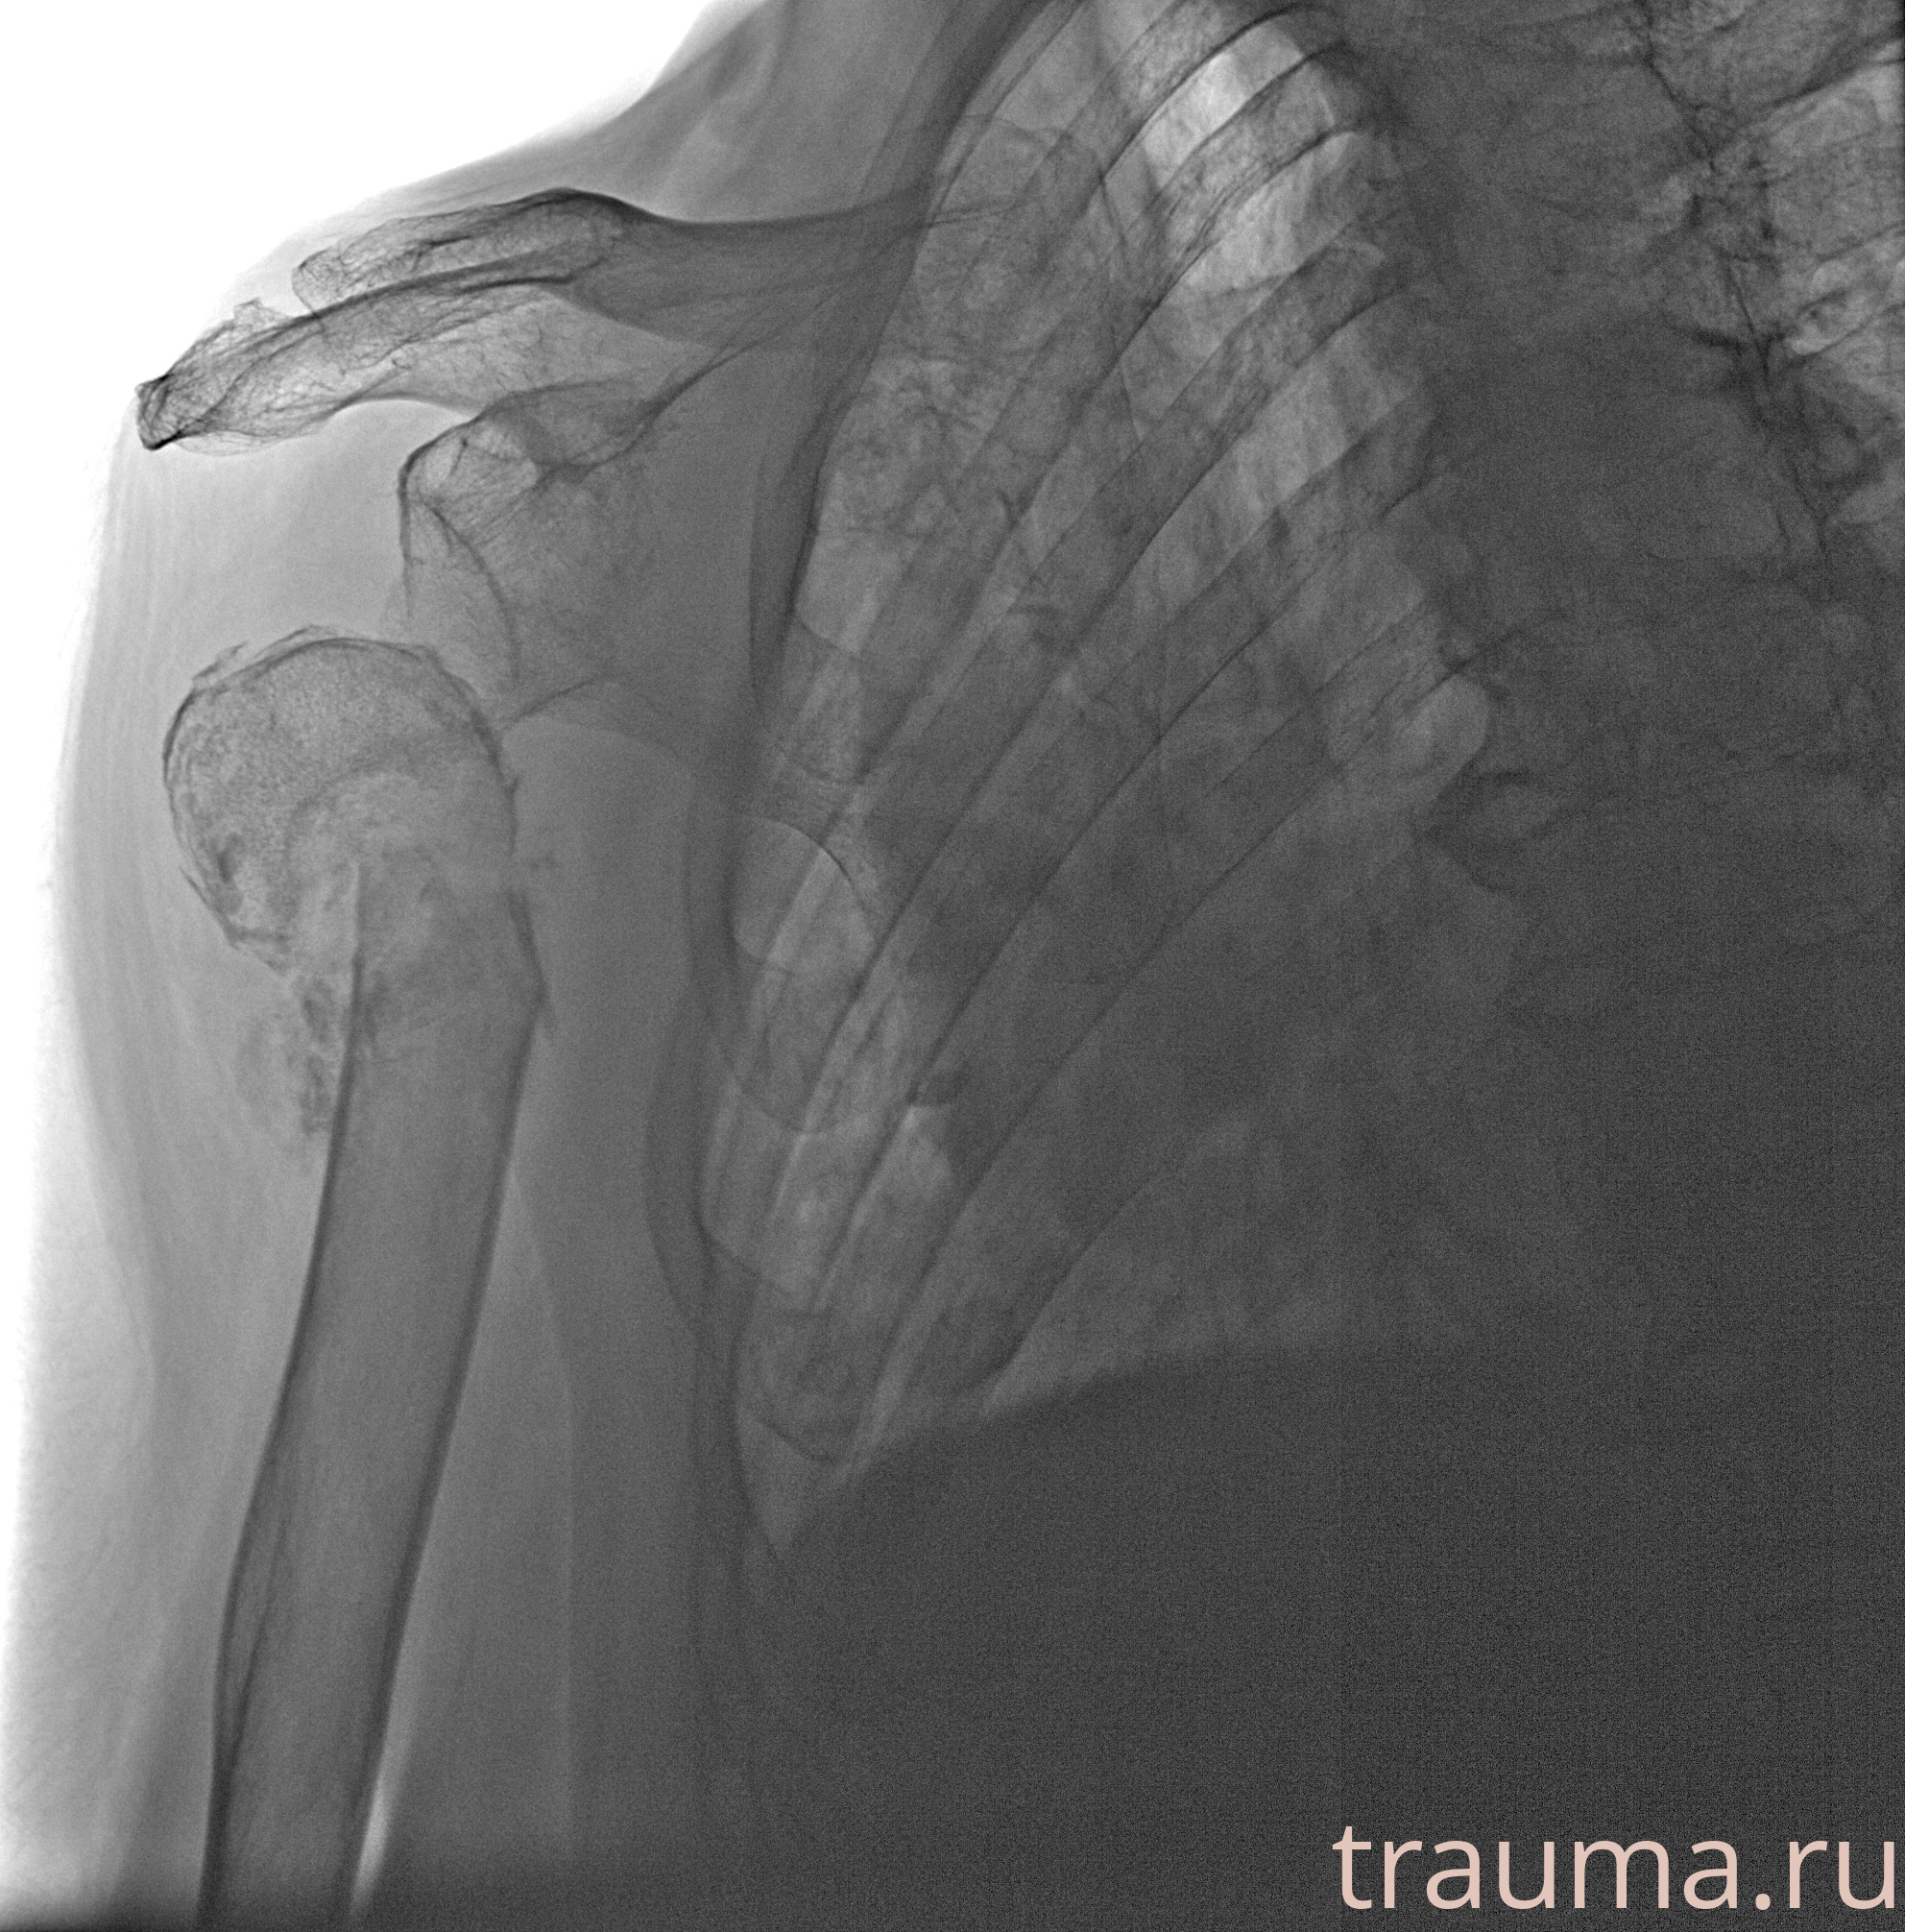

Рентгенограммы

Рентген на дому: по вашему адресу приезжает врач-рентгенолог, травматолог-ортопед с мобильным рентгеновским аппаратом, проводит диагностику травмы или заболевания, делает необходимые рентгенограммы, дает рекомендации по дальнейшему лечению. Получить качественные снимки в домашних условиях возможно благодаря уникальной методике, разработанной МосРентген Центром для института  Склифосовского